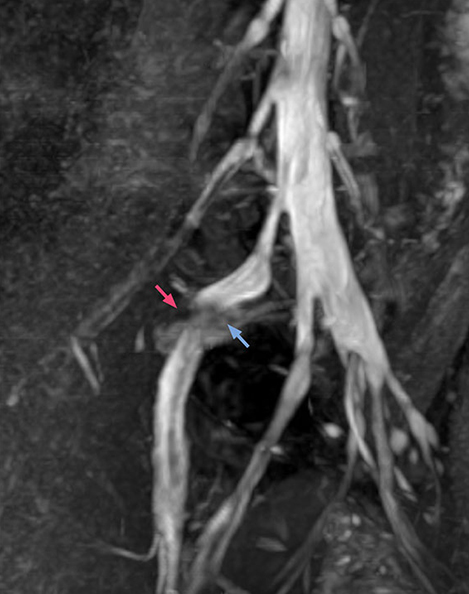

“Although symptoms of typical disc herniation and atypical hernia are very similar, the actual site of herniation is different. It is therefore important to characterize the nerve’s condition both inside and outside of the intervertebral foramina. “Conversely, if we see no abnormality in NerveVIEW, we can assume at least that there is no severe condition that requires surgery. Like this, it can help us avoid unnecessary surgery. NerveVIEW can have a tremendous impact in this way.”

“NerveVIEW is really useful for those cases where a nerve disorder is strongly suspected based on the clinical examination but our regular MRI images do not show any findings. These atypical herniations and spinal canal stenosis, occurring in 5% to 15% of the total lumbar herniation/stenosis cases are our main target when using NerveVIEW,” says Dr. Yabuki.

“The intra-luminal signal of veins, especially around the intervertebral space, can be suppressed well with NerveVIEW. As a result, we can easily observe the detailed nerve structure around the posterior ganglion,” he says. “This is why we use 3D NerveVIEW for intraforaminal stenosis and extraforaminal stenosis/herniation (lateral disc herniation). On the other hand, if herniation is suspected to exist inside the dorsal root ganglion (DRG), balanced TFE or ProSet-FFE is applied. NerveVIEW is not suitable for evaluating the median type of herniation.” The SE-EPI DWI-based method for MR neurography works well for large FOV exams like whole-body MRI, but focal examination of nerves is often limited by the attainable spatial resolution (both inplane and slice direction) and geometric distortion. “3D NerveVIEW achieves higher in-plane resolution – close to our other routine spine sequences – and the source images can be used instead of adding a fat-suppressed T2-weighted sequence,” Tanji says.

According to Tanji, methods such as ProSet FFE, STIR or 3D VISTA are anatomically nonselective because background signals, for instance from blood vessels, often interfere with nerves, which hampers evaluation of details, especially at the peripheral side of the nerves.